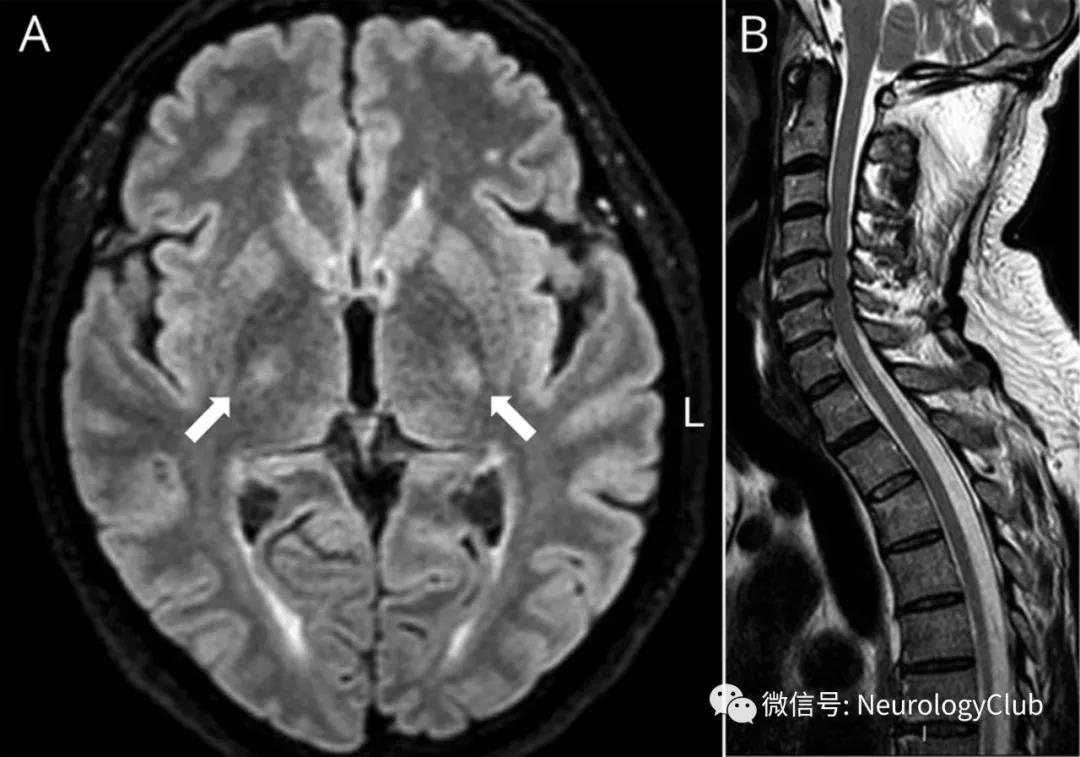

53岁体健男性,出现急性弛缓性截瘫,脊髓感觉平面和尿潴留。查体发现双侧旋前肌漂移试验阳性。MRI可见累及皮质脊髓束(CST),小脑中脚和脊髓的脱髓鞘性非强化病变(图1)。

(图1:T2WI可见双侧皮质脊髓束高信号,从内囊延伸至脑桥[A],以及脊髓纵向延伸的高信号病变[B];FLAIR可见双侧皮质脊髓束[C]和小脑中脚[D]病变;T2快速场回波[T2-FFE]可见脊髓中央部分受累[E,T3水平])